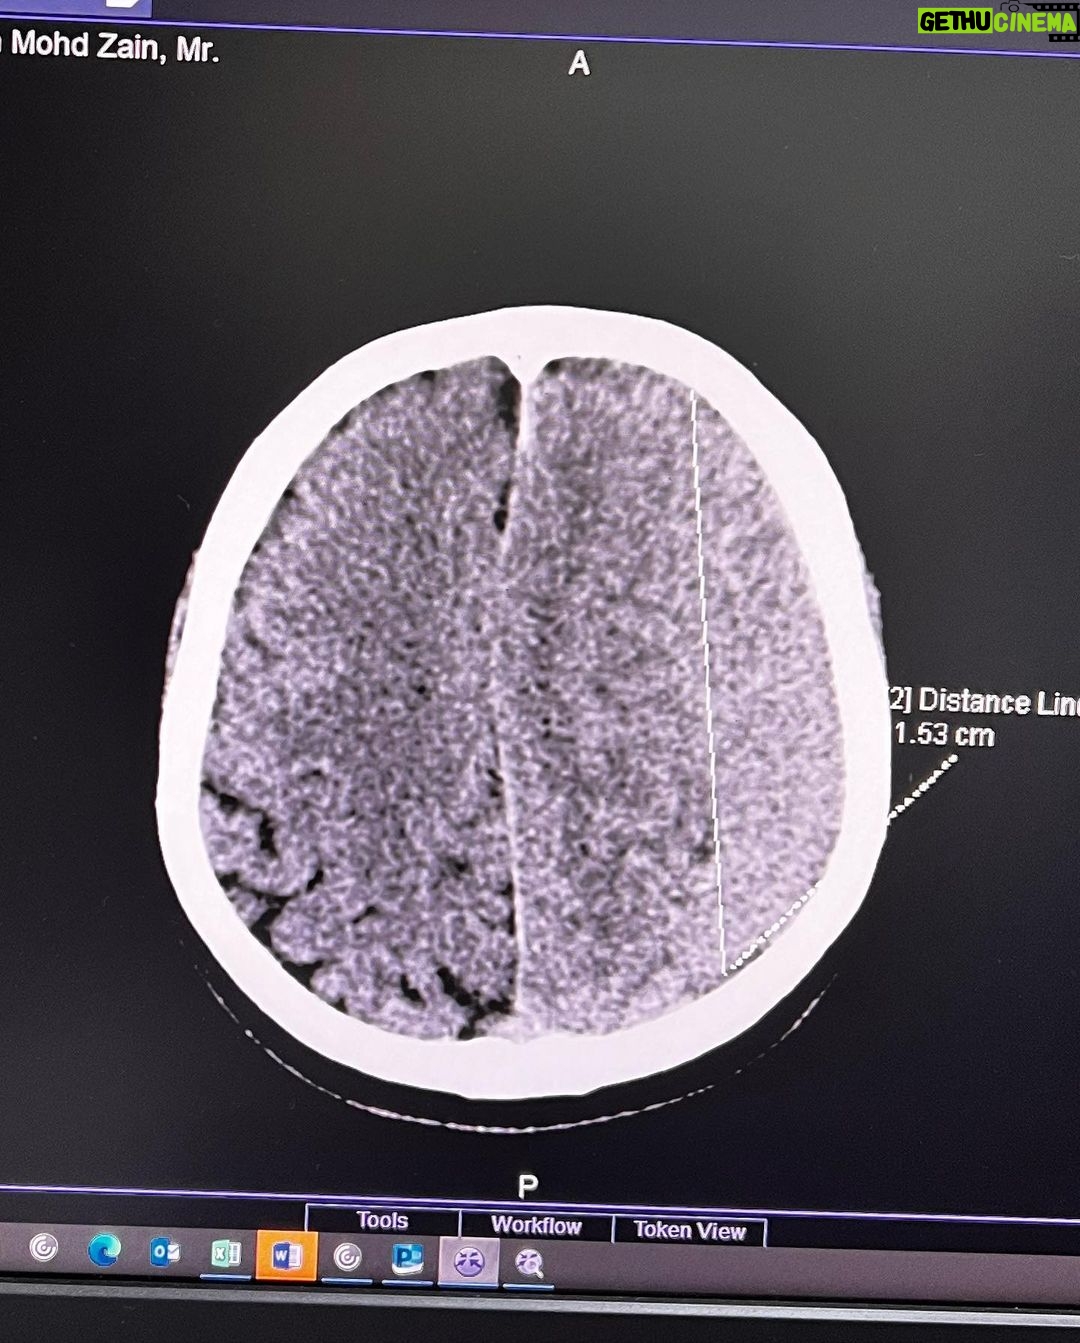

Caption : Kalau anyone you know jatuh kepala terhentak, luaran memang takde apa tapi dalaman maybe boleh jadi pendarahan perlahan. Sejurus dari terjatuh, bila check X-Ray dan CT scan it will tell you nothing, semua clear saja, but 2-3weeks later could turn into your biggest nightmare when the blood has flooded a big part of your brain. My dad realised something was wrong hampir sebulan lepas jatuh, when suddenly he couldn’t really move his right leg. Macam lagging. Sebab dia jatuh terhentak dahi kiri, bila anggota belah kanan yang terjejas, we knew it must be the brain. I picked him up and asked about his very very recent trip to Acheh, he said “Bila Daddy pergi Acheh?”. Ya Allah this very man, is my dad, someone who was very sharp and opinionated, tiba-tiba sangat blur dan slow, jawab sepatah-sepatah. So I spent the whole day uruskan dia, consulted two specialists and one neurosurgeon and when he is finally admitted that night to prepare him for his surgery the following day, he told the family “Daddy tadi drive sendiri datang sini”. My heart sank, I was frantic with worry — takutnya lagi lambat ni lagi banyak memori dia hilang. The brain surgery went well atas izin Allah, thank you to everyone involved. Doktor kata kalau lewat sikit je lagi memang boleh hilang keupayaan bercakap, keupayaan bernafas dan seterusnya koma, sebab otak dah compressed terlalu banyak darah. I jot this here as a reminder for all of us to always jangan tangguh-tangguh kalau hati dah tergerak. Daddy masih tak ingat I bawak dia pi hospital hari tu. Nasib baik kita selfie.Likes : 168141

Caption : Kalau anyone you know jatuh kepala terhentak, luaran memang takde apa tapi dalaman maybe boleh jadi pendarahan perlahan. Sejurus dari terjatuh, bila check X-Ray dan CT scan it will tell you nothing, semua clear saja, but 2-3weeks later could turn into your biggest nightmare when the blood has flooded a big part of your brain. My dad realised something was wrong hampir sebulan lepas jatuh, when suddenly he couldn’t really move his right leg. Macam lagging. Sebab dia jatuh terhentak dahi kiri, bila anggota belah kanan yang terjejas, we knew it must be the brain. I picked him up and asked about his very very recent trip to Acheh, he said “Bila Daddy pergi Acheh?”. Ya Allah this very man, is my dad, someone who was very sharp and opinionated, tiba-tiba sangat blur dan slow, jawab sepatah-sepatah. So I spent the whole day uruskan dia, consulted two specialists and one neurosurgeon and when he is finally admitted that night to prepare him for his surgery the following day, he told the family “Daddy tadi drive sendiri datang sini”. My heart sank, I was frantic with worry — takutnya lagi lambat ni lagi banyak memori dia hilang. The brain surgery went well atas izin Allah, thank you to everyone involved. Doktor kata kalau lewat sikit je lagi memang boleh hilang keupayaan bercakap, keupayaan bernafas dan seterusnya koma, sebab otak dah compressed terlalu banyak darah. I jot this here as a reminder for all of us to always jangan tangguh-tangguh kalau hati dah tergerak. Daddy masih tak ingat I bawak dia pi hospital hari tu. Nasib baik kita selfie.Likes : 168141

Caption : Kalau anyone you know jatuh kepala terhentak, luaran memang takde apa tapi dalaman maybe boleh jadi pendarahan perlahan. Sejurus dari terjatuh, bila check X-Ray dan CT scan it will tell you nothing, semua clear saja, but 2-3weeks later could turn into your biggest nightmare when the blood has flooded a big part of your brain. My dad realised something was wrong hampir sebulan lepas jatuh, when suddenly he couldn’t really move his right leg. Macam lagging. Sebab dia jatuh terhentak dahi kiri, bila anggota belah kanan yang terjejas, we knew it must be the brain. I picked him up and asked about his very very recent trip to Acheh, he said “Bila Daddy pergi Acheh?”. Ya Allah this very man, is my dad, someone who was very sharp and opinionated, tiba-tiba sangat blur dan slow, jawab sepatah-sepatah. So I spent the whole day uruskan dia, consulted two specialists and one neurosurgeon and when he is finally admitted that night to prepare him for his surgery the following day, he told the family “Daddy tadi drive sendiri datang sini”. My heart sank, I was frantic with worry — takutnya lagi lambat ni lagi banyak memori dia hilang. The brain surgery went well atas izin Allah, thank you to everyone involved. Doktor kata kalau lewat sikit je lagi memang boleh hilang keupayaan bercakap, keupayaan bernafas dan seterusnya koma, sebab otak dah compressed terlalu banyak darah. I jot this here as a reminder for all of us to always jangan tangguh-tangguh kalau hati dah tergerak. Daddy masih tak ingat I bawak dia pi hospital hari tu. Nasib baik kita selfie.Likes : 168141

Caption : Kalau anyone you know jatuh kepala terhentak, luaran memang takde apa tapi dalaman maybe boleh jadi pendarahan perlahan. Sejurus dari terjatuh, bila check X-Ray dan CT scan it will tell you nothing, semua clear saja, but 2-3weeks later could turn into your biggest nightmare when the blood has flooded a big part of your brain. My dad realised something was wrong hampir sebulan lepas jatuh, when suddenly he couldn’t really move his right leg. Macam lagging. Sebab dia jatuh terhentak dahi kiri, bila anggota belah kanan yang terjejas, we knew it must be the brain. I picked him up and asked about his very very recent trip to Acheh, he said “Bila Daddy pergi Acheh?”. Ya Allah this very man, is my dad, someone who was very sharp and opinionated, tiba-tiba sangat blur dan slow, jawab sepatah-sepatah. So I spent the whole day uruskan dia, consulted two specialists and one neurosurgeon and when he is finally admitted that night to prepare him for his surgery the following day, he told the family “Daddy tadi drive sendiri datang sini”. My heart sank, I was frantic with worry — takutnya lagi lambat ni lagi banyak memori dia hilang. The brain surgery went well atas izin Allah, thank you to everyone involved. Doktor kata kalau lewat sikit je lagi memang boleh hilang keupayaan bercakap, keupayaan bernafas dan seterusnya koma, sebab otak dah compressed terlalu banyak darah. I jot this here as a reminder for all of us to always jangan tangguh-tangguh kalau hati dah tergerak. Daddy masih tak ingat I bawak dia pi hospital hari tu. Nasib baik kita selfie.Likes : 168141

Caption : Kalau anyone you know jatuh kepala terhentak, luaran memang takde apa tapi dalaman maybe boleh jadi pendarahan perlahan. Sejurus dari terjatuh, bila check X-Ray dan CT scan it will tell you nothing, semua clear saja, but 2-3weeks later could turn into your biggest nightmare when the blood has flooded a big part of your brain. My dad realised something was wrong hampir sebulan lepas jatuh, when suddenly he couldn’t really move his right leg. Macam lagging. Sebab dia jatuh terhentak dahi kiri, bila anggota belah kanan yang terjejas, we knew it must be the brain. I picked him up and asked about his very very recent trip to Acheh, he said “Bila Daddy pergi Acheh?”. Ya Allah this very man, is my dad, someone who was very sharp and opinionated, tiba-tiba sangat blur dan slow, jawab sepatah-sepatah. So I spent the whole day uruskan dia, consulted two specialists and one neurosurgeon and when he is finally admitted that night to prepare him for his surgery the following day, he told the family “Daddy tadi drive sendiri datang sini”. My heart sank, I was frantic with worry — takutnya lagi lambat ni lagi banyak memori dia hilang. The brain surgery went well atas izin Allah, thank you to everyone involved. Doktor kata kalau lewat sikit je lagi memang boleh hilang keupayaan bercakap, keupayaan bernafas dan seterusnya koma, sebab otak dah compressed terlalu banyak darah. I jot this here as a reminder for all of us to always jangan tangguh-tangguh kalau hati dah tergerak. Daddy masih tak ingat I bawak dia pi hospital hari tu. Nasib baik kita selfie.Likes : 168141

Caption : Kalau anyone you know jatuh kepala terhentak, luaran memang takde apa tapi dalaman maybe boleh jadi pendarahan perlahan. Sejurus dari terjatuh, bila check X-Ray dan CT scan it will tell you nothing, semua clear saja, but 2-3weeks later could turn into your biggest nightmare when the blood has flooded a big part of your brain. My dad realised something was wrong hampir sebulan lepas jatuh, when suddenly he couldn’t really move his right leg. Macam lagging. Sebab dia jatuh terhentak dahi kiri, bila anggota belah kanan yang terjejas, we knew it must be the brain. I picked him up and asked about his very very recent trip to Acheh, he said “Bila Daddy pergi Acheh?”. Ya Allah this very man, is my dad, someone who was very sharp and opinionated, tiba-tiba sangat blur dan slow, jawab sepatah-sepatah. So I spent the whole day uruskan dia, consulted two specialists and one neurosurgeon and when he is finally admitted that night to prepare him for his surgery the following day, he told the family “Daddy tadi drive sendiri datang sini”. My heart sank, I was frantic with worry — takutnya lagi lambat ni lagi banyak memori dia hilang. The brain surgery went well atas izin Allah, thank you to everyone involved. Doktor kata kalau lewat sikit je lagi memang boleh hilang keupayaan bercakap, keupayaan bernafas dan seterusnya koma, sebab otak dah compressed terlalu banyak darah. I jot this here as a reminder for all of us to always jangan tangguh-tangguh kalau hati dah tergerak. Daddy masih tak ingat I bawak dia pi hospital hari tu. Nasib baik kita selfie.Likes : 168141

Caption : Kalau anyone you know jatuh kepala terhentak, luaran memang takde apa tapi dalaman maybe boleh jadi pendarahan perlahan. Sejurus dari terjatuh, bila check X-Ray dan CT scan it will tell you nothing, semua clear saja, but 2-3weeks later could turn into your biggest nightmare when the blood has flooded a big part of your brain. My dad realised something was wrong hampir sebulan lepas jatuh, when suddenly he couldn’t really move his right leg. Macam lagging. Sebab dia jatuh terhentak dahi kiri, bila anggota belah kanan yang terjejas, we knew it must be the brain. I picked him up and asked about his very very recent trip to Acheh, he said “Bila Daddy pergi Acheh?”. Ya Allah this very man, is my dad, someone who was very sharp and opinionated, tiba-tiba sangat blur dan slow, jawab sepatah-sepatah. So I spent the whole day uruskan dia, consulted two specialists and one neurosurgeon and when he is finally admitted that night to prepare him for his surgery the following day, he told the family “Daddy tadi drive sendiri datang sini”. My heart sank, I was frantic with worry — takutnya lagi lambat ni lagi banyak memori dia hilang. The brain surgery went well atas izin Allah, thank you to everyone involved. Doktor kata kalau lewat sikit je lagi memang boleh hilang keupayaan bercakap, keupayaan bernafas dan seterusnya koma, sebab otak dah compressed terlalu banyak darah. I jot this here as a reminder for all of us to always jangan tangguh-tangguh kalau hati dah tergerak. Daddy masih tak ingat I bawak dia pi hospital hari tu. Nasib baik kita selfie.Likes : 168141

Caption : Kalau anyone you know jatuh kepala terhentak, luaran memang takde apa tapi dalaman maybe boleh jadi pendarahan perlahan. Sejurus dari terjatuh, bila check X-Ray dan CT scan it will tell you nothing, semua clear saja, but 2-3weeks later could turn into your biggest nightmare when the blood has flooded a big part of your brain. My dad realised something was wrong hampir sebulan lepas jatuh, when suddenly he couldn’t really move his right leg. Macam lagging. Sebab dia jatuh terhentak dahi kiri, bila anggota belah kanan yang terjejas, we knew it must be the brain. I picked him up and asked about his very very recent trip to Acheh, he said “Bila Daddy pergi Acheh?”. Ya Allah this very man, is my dad, someone who was very sharp and opinionated, tiba-tiba sangat blur dan slow, jawab sepatah-sepatah. So I spent the whole day uruskan dia, consulted two specialists and one neurosurgeon and when he is finally admitted that night to prepare him for his surgery the following day, he told the family “Daddy tadi drive sendiri datang sini”. My heart sank, I was frantic with worry — takutnya lagi lambat ni lagi banyak memori dia hilang. The brain surgery went well atas izin Allah, thank you to everyone involved. Doktor kata kalau lewat sikit je lagi memang boleh hilang keupayaan bercakap, keupayaan bernafas dan seterusnya koma, sebab otak dah compressed terlalu banyak darah. I jot this here as a reminder for all of us to always jangan tangguh-tangguh kalau hati dah tergerak. Daddy masih tak ingat I bawak dia pi hospital hari tu. Nasib baik kita selfie.Likes : 168141

Caption : Kalau anyone you know jatuh kepala terhentak, luaran memang takde apa tapi dalaman maybe boleh jadi pendarahan perlahan. Sejurus dari terjatuh, bila check X-Ray dan CT scan it will tell you nothing, semua clear saja, but 2-3weeks later could turn into your biggest nightmare when the blood has flooded a big part of your brain. My dad realised something was wrong hampir sebulan lepas jatuh, when suddenly he couldn’t really move his right leg. Macam lagging. Sebab dia jatuh terhentak dahi kiri, bila anggota belah kanan yang terjejas, we knew it must be the brain. I picked him up and asked about his very very recent trip to Acheh, he said “Bila Daddy pergi Acheh?”. Ya Allah this very man, is my dad, someone who was very sharp and opinionated, tiba-tiba sangat blur dan slow, jawab sepatah-sepatah. So I spent the whole day uruskan dia, consulted two specialists and one neurosurgeon and when he is finally admitted that night to prepare him for his surgery the following day, he told the family “Daddy tadi drive sendiri datang sini”. My heart sank, I was frantic with worry — takutnya lagi lambat ni lagi banyak memori dia hilang. The brain surgery went well atas izin Allah, thank you to everyone involved. Doktor kata kalau lewat sikit je lagi memang boleh hilang keupayaan bercakap, keupayaan bernafas dan seterusnya koma, sebab otak dah compressed terlalu banyak darah. I jot this here as a reminder for all of us to always jangan tangguh-tangguh kalau hati dah tergerak. Daddy masih tak ingat I bawak dia pi hospital hari tu. Nasib baik kita selfie.Likes : 168141

Caption : Kalau anyone you know jatuh kepala terhentak, luaran memang takde apa tapi dalaman maybe boleh jadi pendarahan perlahan. Sejurus dari terjatuh, bila check X-Ray dan CT scan it will tell you nothing, semua clear saja, but 2-3weeks later could turn into your biggest nightmare when the blood has flooded a big part of your brain. My dad realised something was wrong hampir sebulan lepas jatuh, when suddenly he couldn’t really move his right leg. Macam lagging. Sebab dia jatuh terhentak dahi kiri, bila anggota belah kanan yang terjejas, we knew it must be the brain. I picked him up and asked about his very very recent trip to Acheh, he said “Bila Daddy pergi Acheh?”. Ya Allah this very man, is my dad, someone who was very sharp and opinionated, tiba-tiba sangat blur dan slow, jawab sepatah-sepatah. So I spent the whole day uruskan dia, consulted two specialists and one neurosurgeon and when he is finally admitted that night to prepare him for his surgery the following day, he told the family “Daddy tadi drive sendiri datang sini”. My heart sank, I was frantic with worry — takutnya lagi lambat ni lagi banyak memori dia hilang. The brain surgery went well atas izin Allah, thank you to everyone involved. Doktor kata kalau lewat sikit je lagi memang boleh hilang keupayaan bercakap, keupayaan bernafas dan seterusnya koma, sebab otak dah compressed terlalu banyak darah. I jot this here as a reminder for all of us to always jangan tangguh-tangguh kalau hati dah tergerak. Daddy masih tak ingat I bawak dia pi hospital hari tu. Nasib baik kita selfie.Likes : 168141